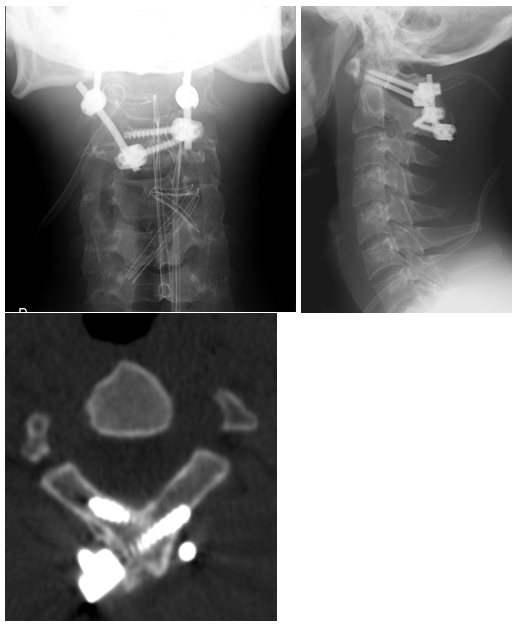

A 27-year-old male patient with no relevant medical or surgical history and working in the military army, was observed in an Orthopedics consultation, referred from primary health care for complaints of neck pain, without irradiation to the upper limbs, associated with limitation of mobility, especially in sagittal plane movements, with 4 months of evolution (Neck Disability Index (NDI) of 26). The patient denied a history of trauma, but reported upper respiratory infection (pharyngitis) one month before the onset of cervical pain. Physical examination revealed decreased cervical mobility, without other major findings. The diagnostic study began with two-plane cervical radiography (Figure 1), with an approximate ADI value of 10.5 mm, as well as dynamic radiographs (Figure 2), which demonstrated C1-C2 dynamic instability (ADI of 10.9 and 9.8 mm respectively). The CT study confirmed atlanto-axial sub dislocation and excluded the presence of fractures or facet subluxations (Figure 3). The study was complemented by magnetic resonance imaging, which confirmed atlanto-axial sub dislocation, associated with inflammation and thickening of the paravertebral soft tissues, with transverse ligament incompetence (Figure 4 - magnetic resonance imaging). Due to the decreased mobility of the upper cervical spine, the possibility of Meningitis was raised. Blood analytical study showed marginal elevation of C-Reactive Protein (28 mg/L), thus, the hypothesis of Grisel's Syndrome was placed. The patient was initially treated with the use of a Minerva cervical collar and broad-spectrum empirical antibiotic therapy with Ceftriaxone for 6 weeks, but after this period, there was unfavorable clinical evolution, with worsening of cervical pain and functional status (NDI of 30). Surgical treatment was therefore elected, through posterior atlanto-axial fixation, which is in accordance with other cases published in the literature.2The surgery was uneventful and the patient had a favorable clinical course, with significant improvement in neck pain and joint mobility, with an improvement in the NDI from 30 to 5. Radio graphically, a reduction in atlanto-axial subluxation was confirmed (Figure 5), which remained stable until 5 years of follow-up. There were no late complications and the patient resumed his normal activities.

Figure 3  TC image with C1-C2 dislocation.

Figure 5  Radiografic result 5 years after surgery.